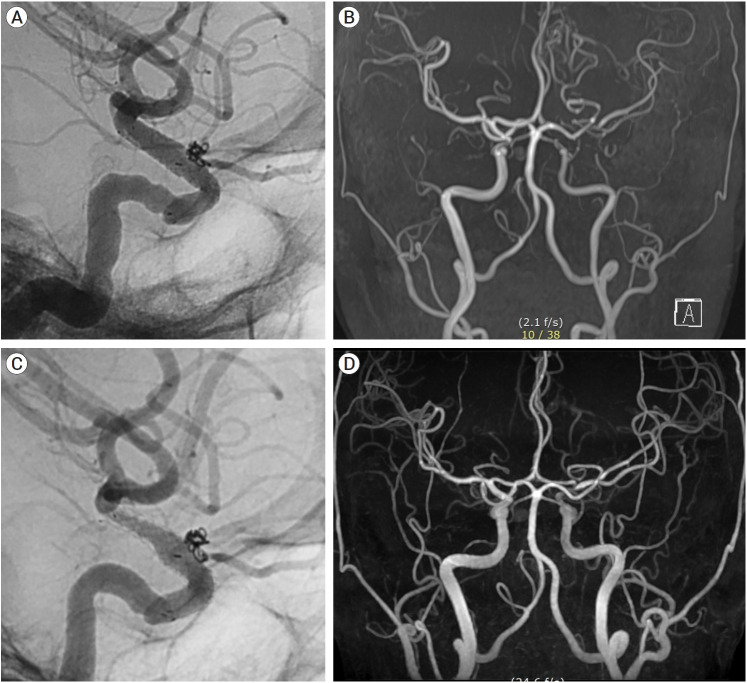

Objective: Stent-assisted coil embolization (SAC) is an effective method of treating intracranial aneurysms. The aim of the study was to assess the safety and efficacy of the new ACCERO stent for the treatment of cerebral aneurysms.

Methods: It was a retrospective, single-center study. Nine ruptured and 41 unruptured cerebral aneurysms were treated using the ACCERO stent between February 2021 and December 2023. Patient demographics, aneurysm characteristics, procedural parameters, grade of occlusion, complications, and clinical outcomes were analyzed. Follow-up was conducted with magnetic resonance angiography (MRA) or Digital subtraction angiography (DSA) was performed 6 to 12 months after the procedure.

Results: The ACCERO stent deployment was attempted in 51 cases, with replacement by the Neuroform Atlas stent in 1 case. Successful stent deployment was achieved in 50 cases, and appropriate wall apposition to the parent artery. The average clinical follow-up period was 17.1 months. Intimal hyperplasia was observed in 1 case, but no other clinical complications related to the stent occurred. Favorable clinical outcomes were observed in 92% of patients (46/50), including those with subarachnoid hemorrhage. Immediate favorable angiographic outcomes and complete occlusion were achieved in 90% (45/50) and 74% (37/50) of cases, respectively. Among the 45 patients who had imaging follow-up, favorable angiographic outcomes and complete occlusion were observed in 93.3% (43/45) and 82.2% (37/45) of cases, respectively.

Conclusions: The ACCERO stent is a braided-type stent that requires more attention than stents, such as the Neuroform Atlas or Enterprise stents. However, since the struts of the stent are fully visible, it can be more useful in treating challenging aneurysms once the user becomes familiar with its use.